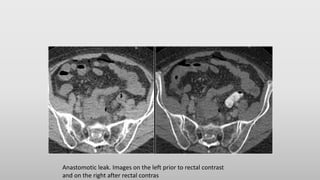

Anastomosis leakage

• Leakage after bowel surgery is a great clinical problem.

• A NECT without any oral or rectal contrast is needed to compare with

the CECT with rectal contrast to know the hyperdense stuff outside

the bowel is leakage or some post-operative material, dense bowel

content or contrast from an earlier examination.

Anastomotic leak. Images on the left prior to rectal contrast

and on the right after rectal contras

Anastomosis leakage • Leakageafter bowel surgery is a great clinical problem. • A NECT without any oral or rectal contrast is needed to compare with the CECT with rectal contrast to know the hyperdense stuff outside the bowel is leakage or some post-operative material, dense bowel content or contrast from an earlier examination.

Anastomotic leak. Imageson the left prior to rectal contrast and on the right after rectal contras

• #54 Compare the NECT without oral or rectal contrast on the left with the images on the right after rectal contrast. There is no doubt, that contrast in the fluid collection in the right lower abdomen is the result of leakage from the bowel (arrow).